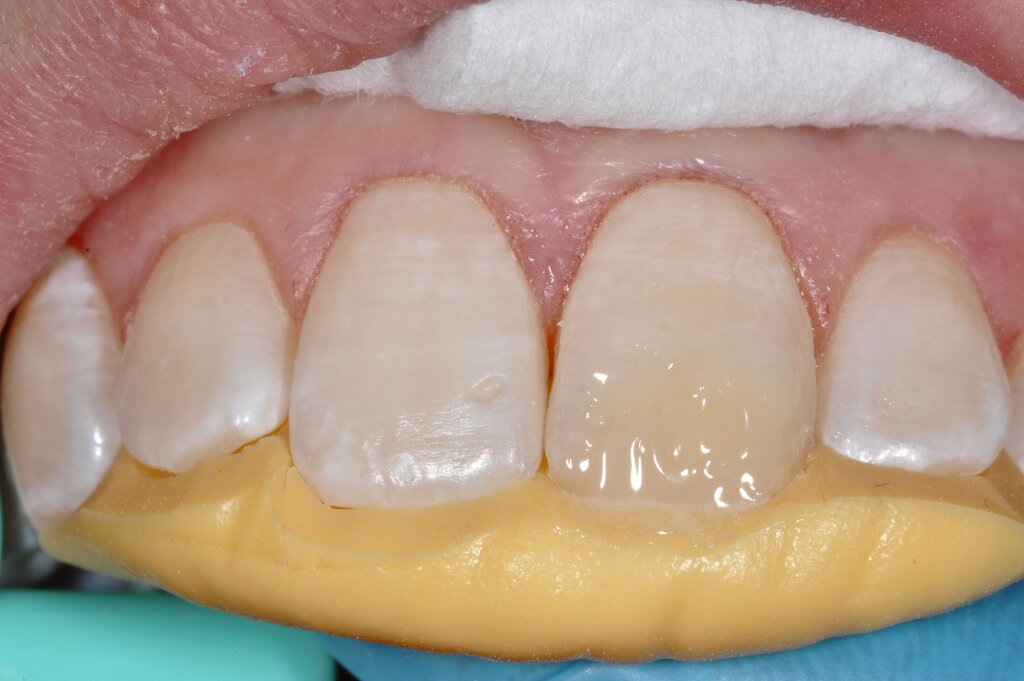

Die Versorgung der MIH-Frontzähne entspricht dem Vorgehen im Seitenzahnbereich. Problematisch ist die Maskierung der Opazitäten. Dazu müssen opake Komposite verwendet werden und es muss eine Schichtstärke von circa 1,5 mm garantiert sein (Abbildung 9).